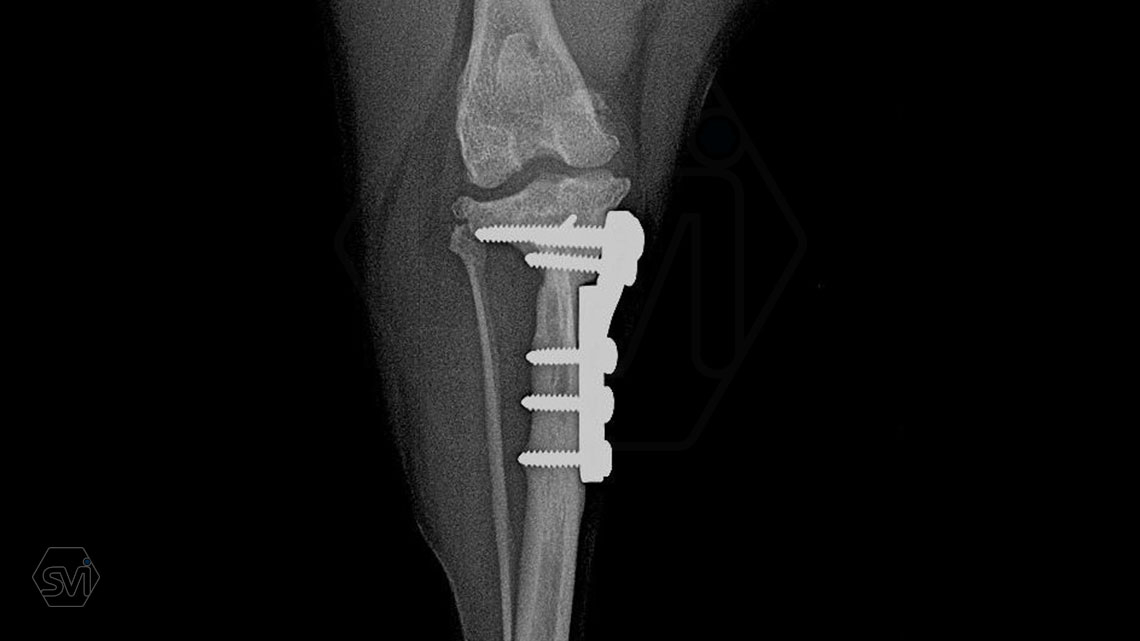

The attached x-rays were taken during the check-up of a 6.5-year-old Yorkshire terrier that underwent TPLO-M surgery a year and a half ago, the limb is fully loaded, it shows no lameness, the osteotomized parts are well ossified, the bone stock has not been resorbed.

A mellékelt képek egy másfél évvel ezelőtt TPLO-M műtéten átesett, most 6,5 éves yorkshire terrier kontrollja során készült, a végtagot teljesen terheli, sántaságot nem mutat, az oszteotomizált részek jól csontosodtak, a csontállomány nem szívódott fel.